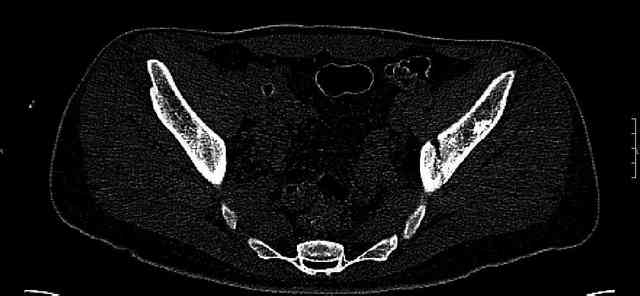

Some more images. Does it help to guess which part of the acetabulum is displaced?